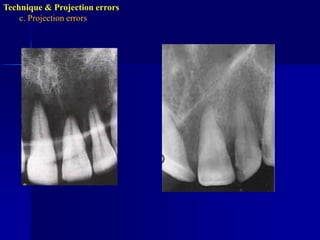

Technique & Projection errorsc. Projection errorsIncorrect vertical angulationIt will lead to:Elongated image due to insufficient v. angulation ( too flat), or

Shortened image due to excessive v. angulation ( too steep)Technique & Projection errorsc. Projection errors

Technique & Projection errorsc. Projection errors

Technique & Projection errorsc. Projection errorsIncorrect horizontal angulationIs the appearance of the interproximal surfaces of the adjacent teeth over each other. This is due to improper H.A. due to improper alignment of the C.R. through the contact points i.e. not // to interproximal surfaces.